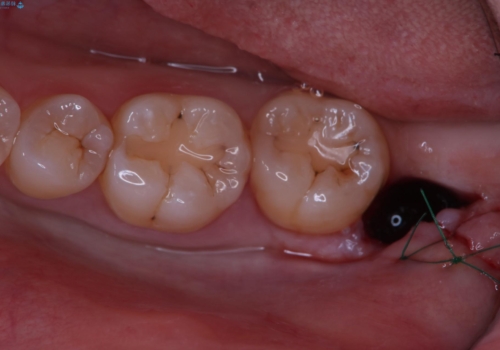

局所麻酔後に必要に応じて歯肉の切開や、歯を分割して抜歯を行います。

抜歯後は糸で縫って、1週間後に抜糸に来ていただきます。